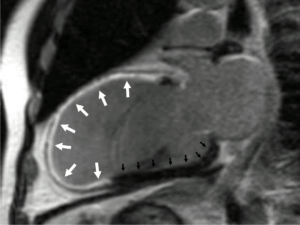

Beispiele für Untersuchungsbefunde:

2. Darstellung einer großen Vorderwandnarbe (weiß, Pfeile) nach Kontrastmittelapplikation (normaler Herzmusskel schwarz, Pfeile).